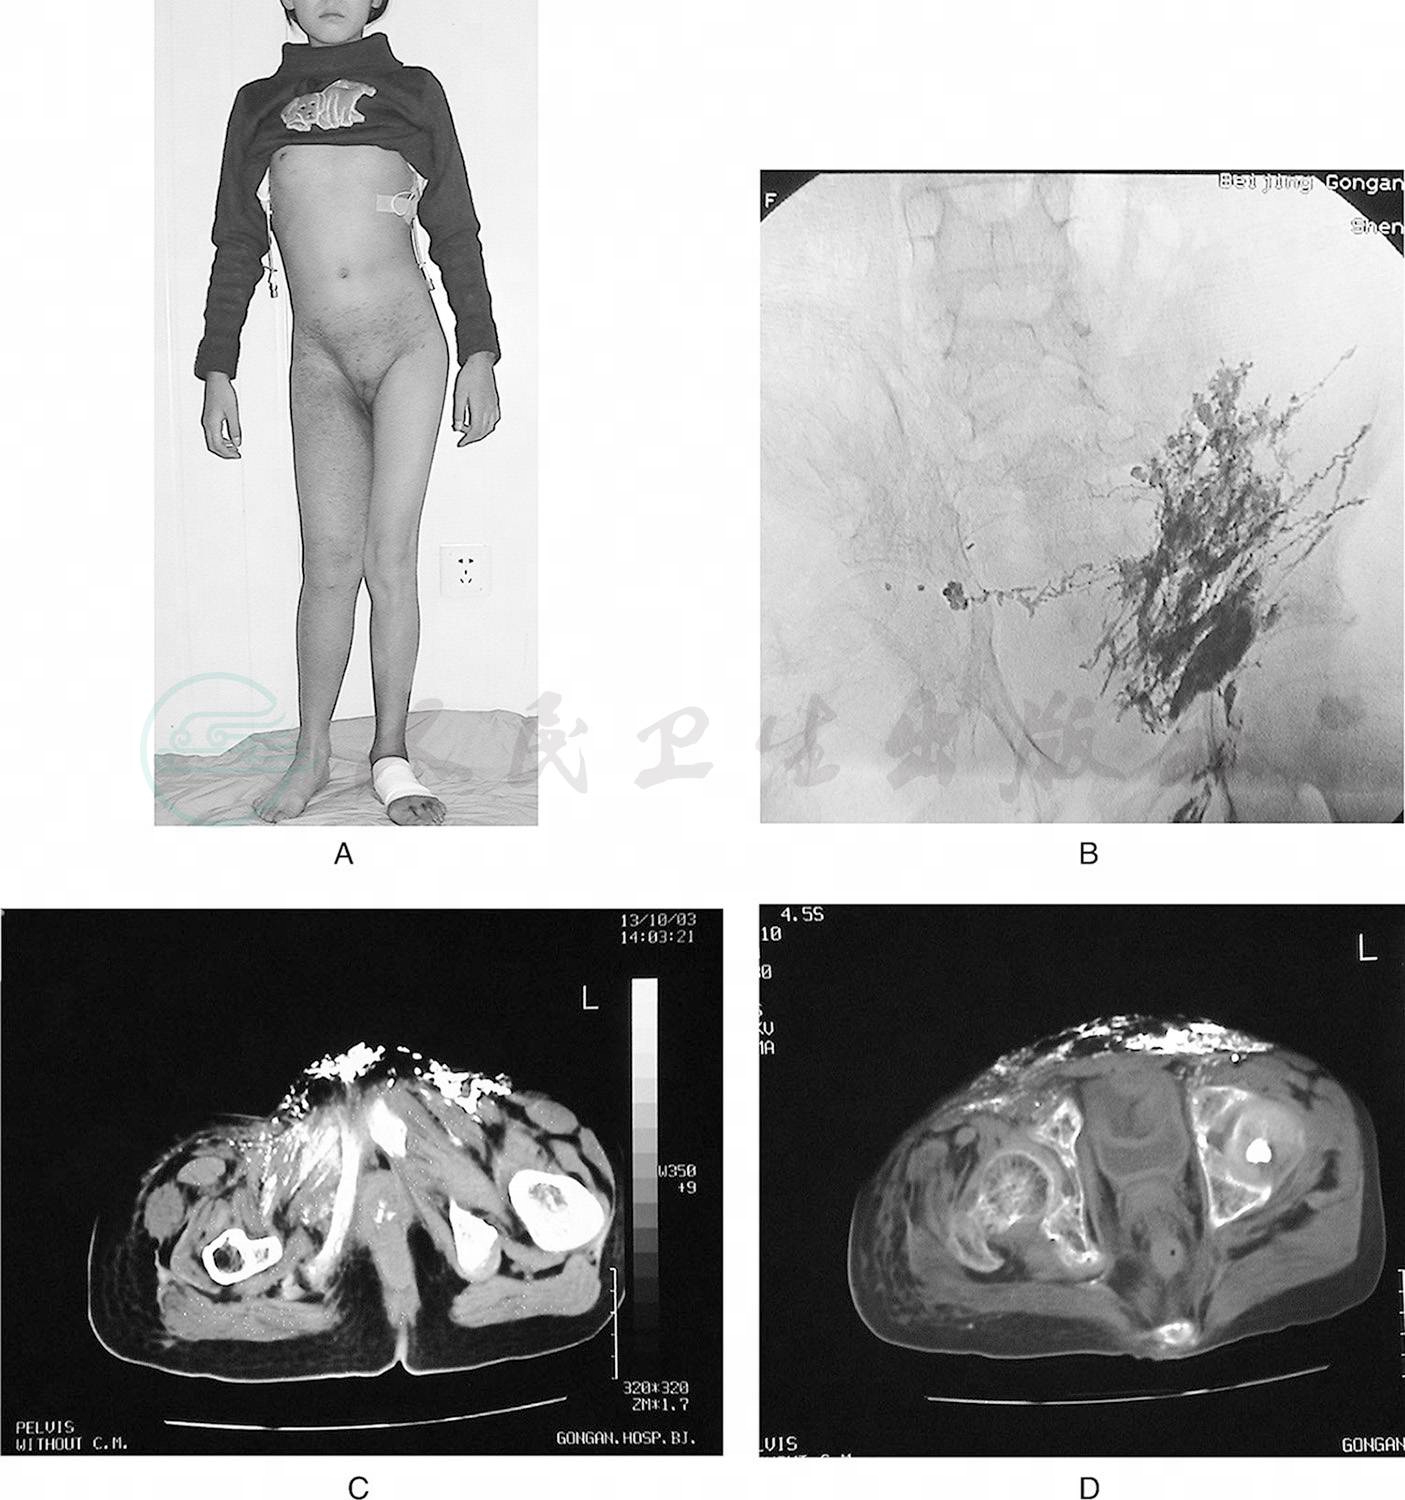

我组乳糜性腹水病例中,有一对来自吉林的母子同患乳糜性腹水,影像学均表现为原发性腹膜后淋巴管发育不全。儿子同时有乳糜性胸水和下肢淋巴水肿(图1)。

图1母子同患乳糜胸腹水

母亲45岁,A.核素淋巴显像:腹股沟淋巴结核素浓聚,腰淋巴干未显影。儿子18岁,伴有右下肢淋巴水肿,经右足背直接淋巴管造影显示:B.右下肢淋巴水肿,小腿淋巴管网状扩张;C.腹膜后淋巴管发育不全,右腹股沟有淋巴管侧支代偿形成;D.经右耳后淋巴管直接淋巴管造影显示:颈干形成不全,未汇入颈静脉角区域,并向颈前反流。母亲保守治疗腹水消失,儿子行腹腔静脉转流术良好控制